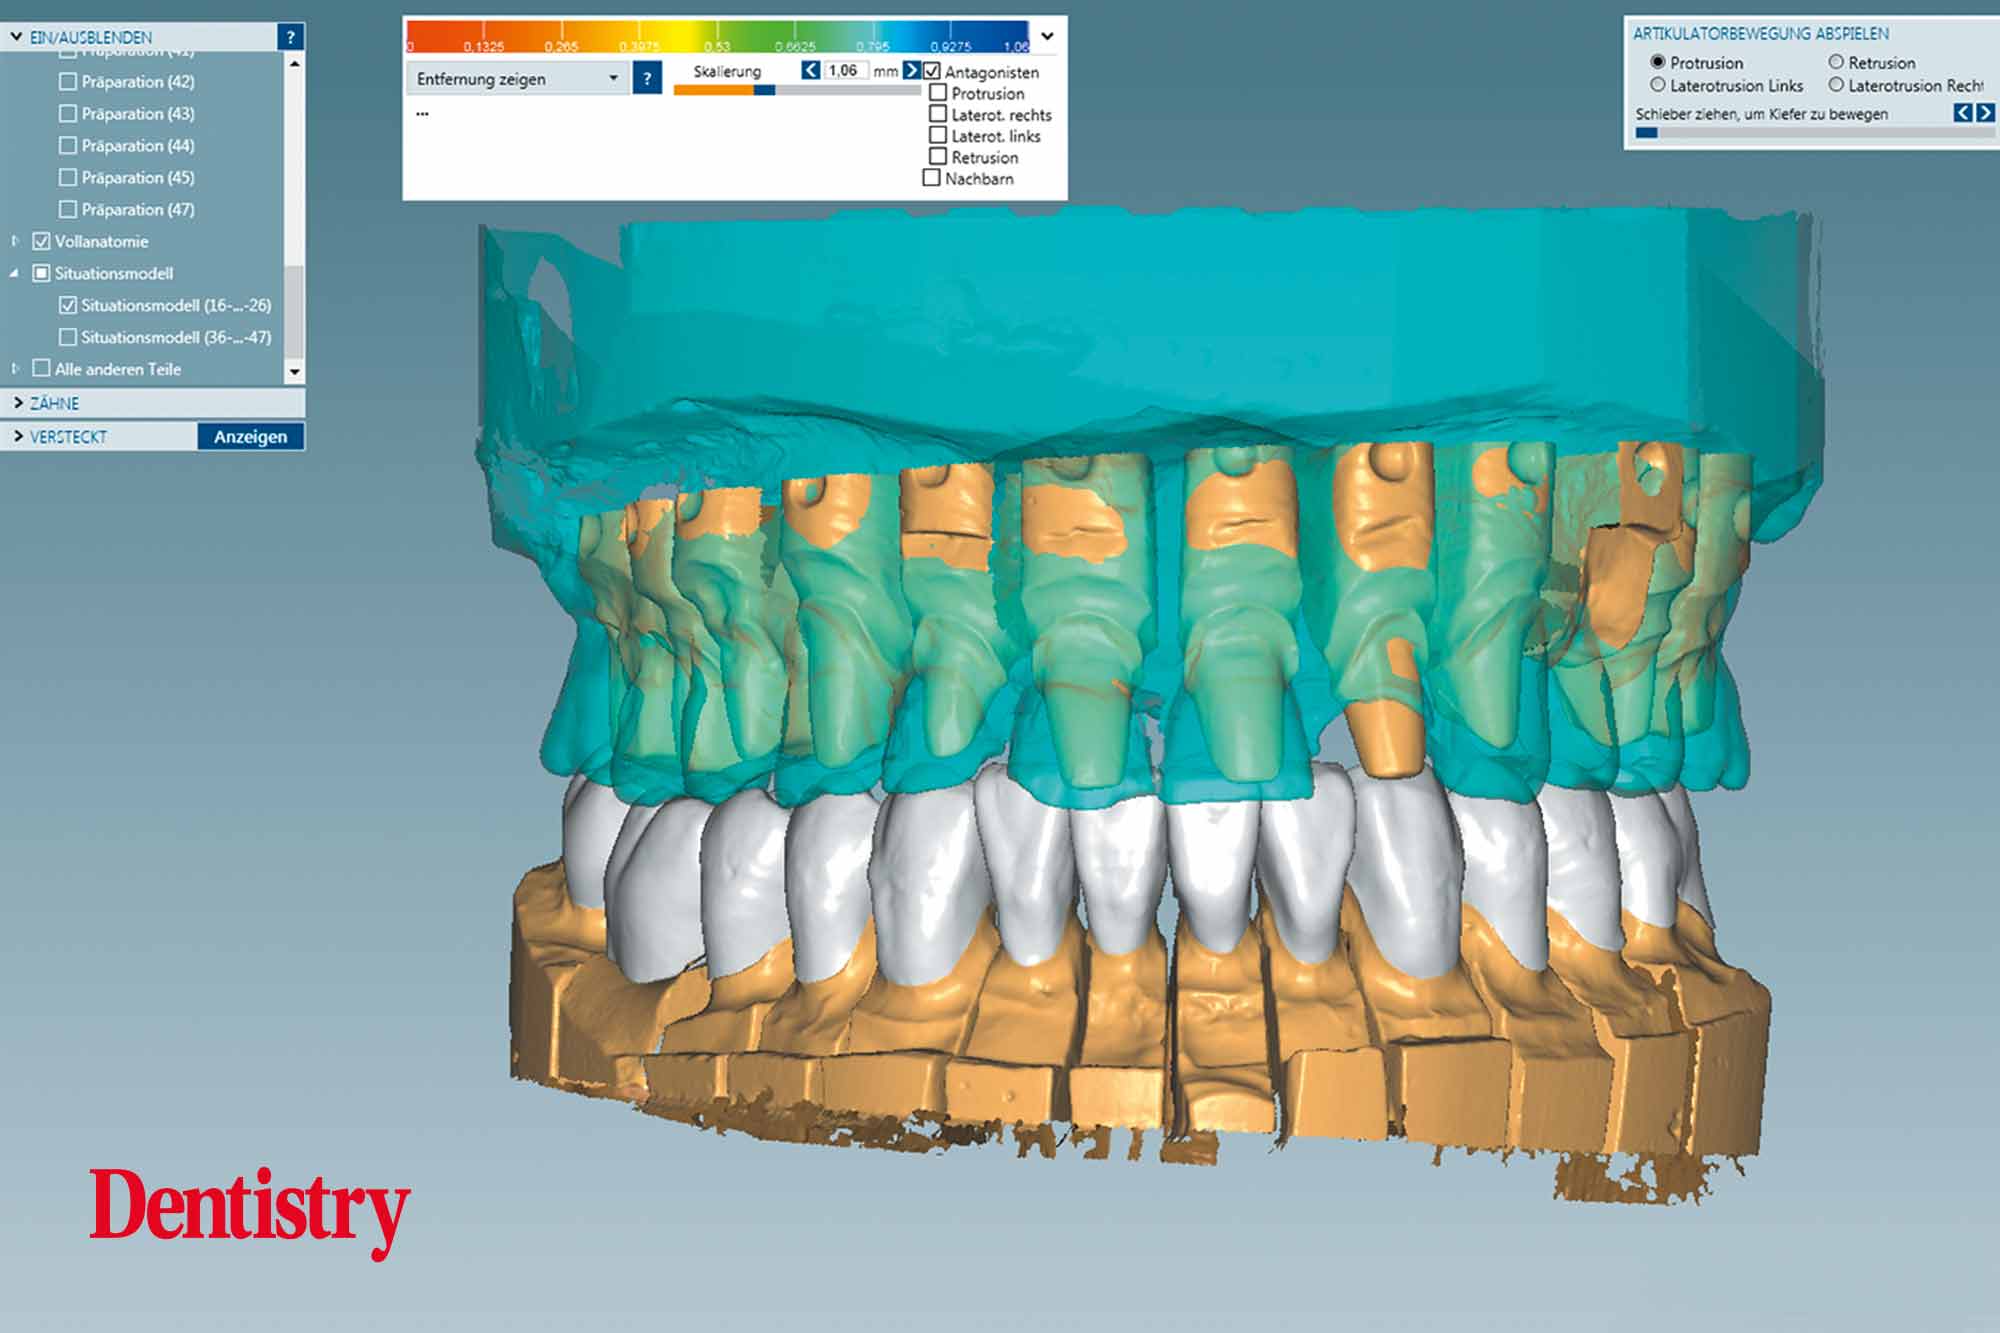

The scanned models were evaluated on a virtual 11 articulator. Temporary Ceramill PMMA (Amann Girrbach) transparent acrylic crowns were CAD planned (Figures 3a to 3d).

Patient data including condylar movements were recorded by the software. Using the Initial situation software’s customised incisal guide unit, the incisal guide pin was adjusted on the splitex plate to the desired cuspal inclinations on the virtual temporary crowns (Figure 4).

All patient parameters including condylar inclination were transferred to the Ceramill Artex articulator and the lateral and protrusive excursions were established while having no contact with the anterior teeth (Figures 5 to 8).